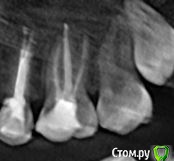

pustoe Опубликовано 13 марта, 2016 Автор Поделиться Опубликовано 13 марта, 2016 Уважаемые врачи, помогите советом! После тройного перелечивания 25 зуба я пол года не обращала внимания на то что чувствую боль при надкусывании. Но надоедает, знаете ли. Ещё раз попыталась понять точно ли 25 болит и выяснила, что боль в 26 зубе. Только при давлении на 1 определённый участок. И боль возникает только при жевании или когда я самостоятельно зубами пытаюсь найти этот участок. На осмотре зуб никак не реагирует ни на давление, ни на воздух, ни на холодную воду. Ну и главное - он мёртвый. Год назад обратилась в клинику, где проводили депульпирование зуба. На снимках врач не нашёл патологий, при ощупывании десны заметил боль в области 28 зуба. Хороший снимок 28 сделать не получилось, направили к хирургу.Посетила хирурга, сделали 3д-томографию. Хирург сказал, что удалять 28 зуб не нужно и проблема в 26, на снимке видна гранулёма. Ниже приложила 2 снимка от хирурга (декабрь 2014 г.). Обратилась в ту же клинику, где лечила 26 зуб , попросила 1) сменить врача, 2) лечить по гарантии. Зуб пролечили (февраль 2015 г.), результаты лечения на снимке №299 (сделан в ноябре 2015 г). Боли при надкусывании появились спустя недели 2-3. Далее в связи с переездом в другой город, не было возможности вновь обратиться к лечащему врачу, поэтому обратилась в новую клинику с целью удалить зуб или наткнуться на профессионалов, которые вылечат меня. В ней посчастливилось услышать аж два мнения разных врачей: терапевт сказал, что все дураки и плохо меня пролечили, надо заново перепломбировать каналы и закладывать лекарства, плюс на 25 зубе обнаружил гранулёму (осмотра физически не произвёл в связи с тем, что на час задержал мой приём и за мной был другой пациент, поэтому времени на меня у врача не было). Второй врач-пародонтолог предложил сделать резекцию. Я согласилась на второй вариант, при посещении пародонтолога описала историю зуба, врач засомневалась в наличии гранулёмы, хотя сказала, что на снимке гранулёма видна. Но раз пришла, решили резать. Разрезали десну, ткани здоровые, куча камня. Провели кютераж, гранулёму не нашли. Насколько я поняла, глубоко рыться в корнях врач не стала в связи с тем, что вариант с гранулёмой отмела. Прошёл месяц, две недели назад начала жевать на этой стороне, боли вернулись. Я в растерянности, вы, врачи с форумов, всегда советуете обратиться очно к специалистам, но я в той ситуации, когда это не помогает. Можно сходить и удалить зуб, но не хочется терять его, да и когда я шла к врачам с этой целью, меня убедили сохранить зуб.Скажите, что мне делать? Что вы видите на снимках ноября (самый актуальный снимок). Как может врач видеть на снимке гранулёму, а при разрезе десны не обнаружить её (в квалификации этого врача сомнений нет)? Как мне избавиться от боли? Может кто-то из вас работает в Санкт-Петербурге и готов взяться за меня?Хочу от вас конкретные советы и комментарий к снимку. Ссылка на комментарий

pustoe Опубликовано 13 марта, 2016 Автор Поделиться Опубликовано 13 марта, 2016 Ниже актуальный снимок в лучшем качестве Ссылка на комментарий